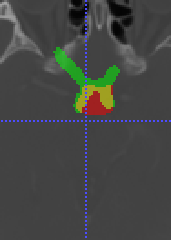

In Chapter 6, we propose an end-to-end, atlas-free 3D convolutional deep learning framework for fast and fully automated whole-volume HaN anatomy segmentation [115]. Our deep learning model, called AnatomyNet, segments OARs from head and neck CT images in an end-to-end fashion, receiving whole-volume HaN CT images as input and generating masks of all OARs of interest in one shot. AnatomyNet is built upon the popular 3D U-net architecture, but extends it in three important ways: 1) a new encoding scheme to allow auto-segmentation on whole-volume CT images instead of local patches or subsets of slices, 2) incorporating 3D squeeze-and-excitation residual blocks in encoding layers for better feature representation, and 3) a new loss function combining Dice scores and focal loss to facilitate the training of the neural model. These features are designed to address two main challenges in deep-learning-based HaN segmentation: a) segmenting small anatomies (i.e., optic chiasm and optic nerves) occupying only a few slices, and b) training with inconsistent data annotations with missing ground truth for some anatomical structures. We collect 261 HaN CT images to train AnatomyNet, and use MICCAI Head and Neck Auto Segmentation Challenge 2015 as a benchmark dataset to evaluate the performance of AnatomyNet. The objective is to segment nine anatomies: brain stem, chiasm, mandible, optic nerve left, optic nerve right, parotid gland left, parotid gland right, submandibular gland left, and submandibular gland right. Compared to previous state-of-the-art results from the MICCAI 2015 competition, AnatomyNet increases Dice similarity coefficient by 3.3% on average. AnatomyNet takes about 0.12 seconds to fully segment a head and neck CT image of dimension , significantly faster than previous methods. In addition, the model is able to process whole-volume CT images and delineate all OARs in one pass, requiring little pre- or post-processing. We demonstrate that our proposed model can improve segmentation accuracy and simplify the auto-segmentation pipeline. These contributions are released as an open-source software package called AnatomyNet, which is publicly available555https://github.com/wentaozhu/AnatomyNet-for-anatomical-segmentation. Portions of this chapter were published as part of [115].